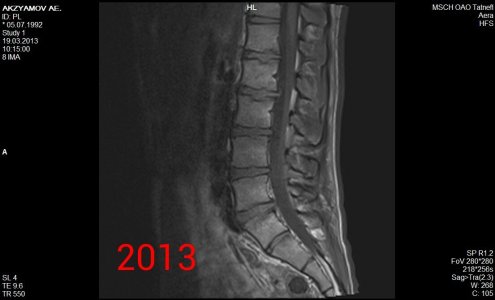

Здравствуйте! Я парень, мне 21 год, рост 190, вес 90, у меня поясничные грыжи l1-l2 1,8 мм, l2-l3 3,5 мм, l5-s1 4,4 мм, беспокоит уже 1,5 года слабость в ногах сначала была боль в левой ноге затем исчезла, и появилась постепенно слабость с внешней стороны квадрицепса до большого пальца ноги, и справа от колена по внешней стороне до большого пальца вниз, больше интересует непостоянность этих симптомов, то есть они могут вообще исчезать на один день и появляться на другой, могут появиться просто когда лежал телевизор смотрел и при этом спина вообще не болит, и в ногах боли тоже нет, невролог проводивший осмотр направлял на вич, гепатит, сифилис все чисто. Если начинаю пить прозерин по 2 таблетки в день все как рукой снимает. Ниже приведены все снимки и заключения имеющиеся на руках.Что это может быть, почему слабость может так быстро исчезать и появляться снова, грыжи то на месте может это что то другое? И еще хотелось бы узнать ваше мнение по поводу записи в заключении 2013 года (Арахноидальная киста в мягких тканях на уровне межостистых отростков L5-S1 7x8-8x2 мм) она не может сдавливать нервы?